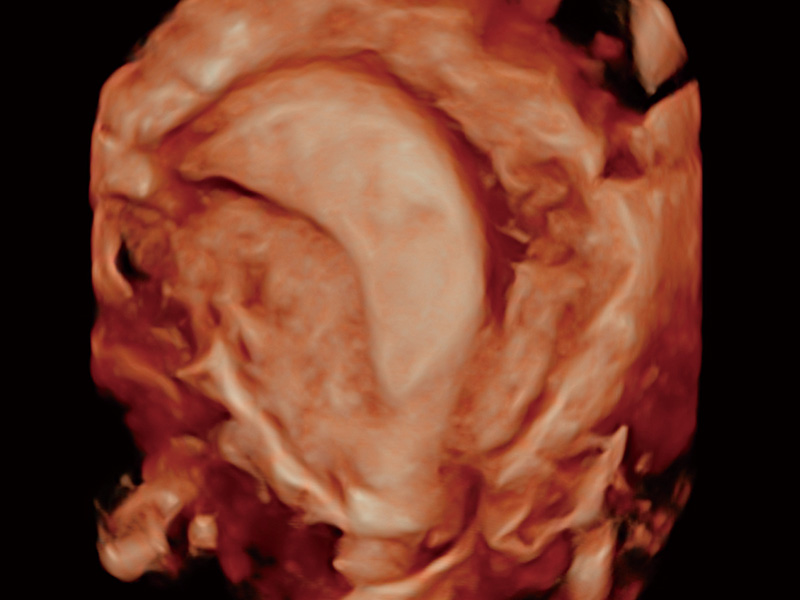

腔内容积探头

腔内三维成像技术获得显著提升,超大扇角在满足日常基础扫查的同时,支持卵泡自动测量及多种三维渲染模式,为您提供更多的诊断信息,尤其是在子宫畸形的诊断,内膜及肿瘤占位观测中起到了重要的作用。

中央型宫腔粘连

子宫内膜息肉